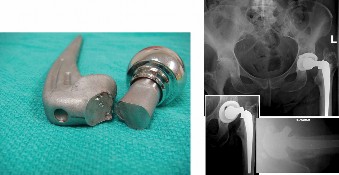

An 82-year-old woman, with a BMI of 33.9 and history of total hip replacement performed 8 years ago, sustaine…